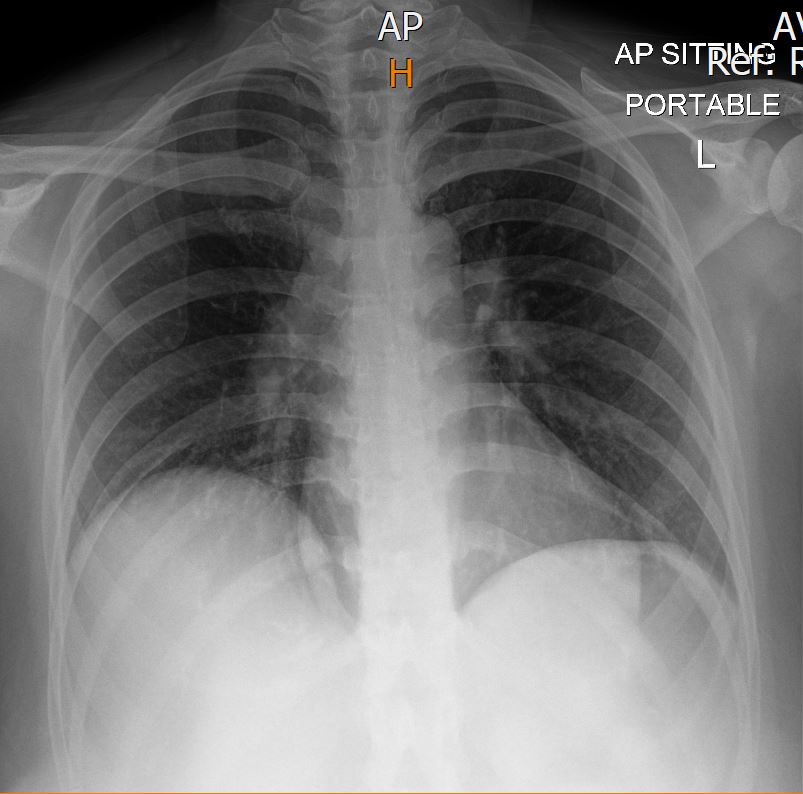

A 42-year-old woman with no known medical illness presented to the ED with shortness of breath for the past 5 days, which acutely worsened a few hours ago. On physical examination, she was tachypneic, lethargic with altered mental status, normotensive but tachycardic, and had an oxygen saturation of 92% on room air. Lung auscultation revealed reduced breath sounds bilaterally, and heart auscultation showed no murmurs. Her chest X-ray was clear, but the ECG showed a typical S1 Q3 T3 pattern.